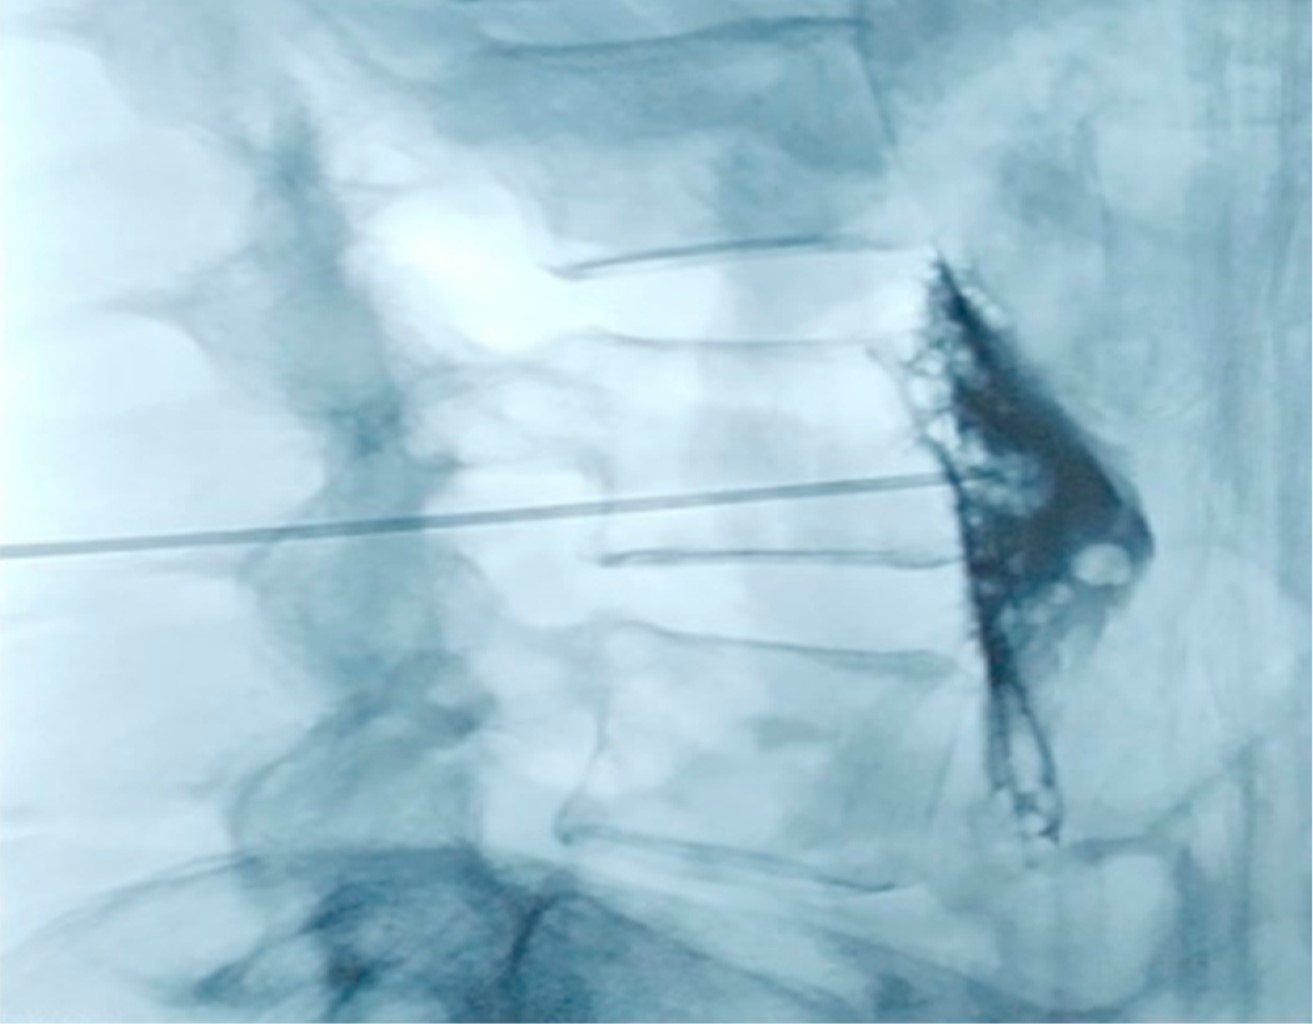

Bloqueo simpático lumbar. La distribución anatómica de la cadena simpática lumbar es de las más variables de todo el sistema simpático. Los ganglios pueden estar distribuidos de manera segmentada o agrupados entre la porción cefálica del cuerpo L2 y la zona caudal del cuerpo L4. El abordaje clásico se realiza mediante fluoroscopia (Figura 2), aunque también existen descripciones guiadas por ultrasonido.

No existe una gran cantidad de ensayos clínicos que evalúen esta técnica en el tratamiento de SDRC de miembro inferior. Se ha propuesto utilizar primero anestésico local como bloqueo diagnóstico y, posteriormente, en caso de éxito se han sugerido bloqueos con alcohol, fenol, termocoagulación por radiofrecuencia e incluso crioablación.25